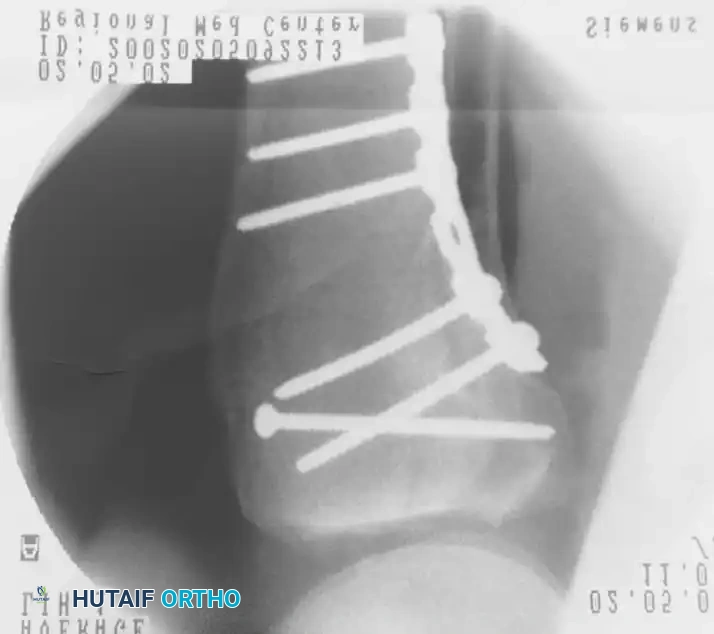

ثالثا استراتيجيات التثبيت الداخلي

بعد إعادة بناء سطح المفصل، يتم تثبيته بشكل نهائي باستخدام مسامير وشرائح معدنية مصممة خصيصا لتلائم شكل عظمة الساق العلوية.

تثبيت الكسر باستخدام الشرائح والمسامير

في الكسور المعقدة التي تشمل جانبي الركبة، غالبا ما يتطلب الأمر استخدام شريحتين معدنيتين لضمان عدم انهيار العظم تحت تأثير وزن الجسم.

استخدام شريحتين لتثبيت الكسور المعقدة

يقوم الجراح باستخدام جهاز الأشعة التداخلية للتأكد من استعادة المحور الميكانيكي للساق، والتأكد من عدم اختراق أي مسامير لسطح المفصل.

التصوير الإشعاعي أثناء الجراحة للتأكد من التثبيت